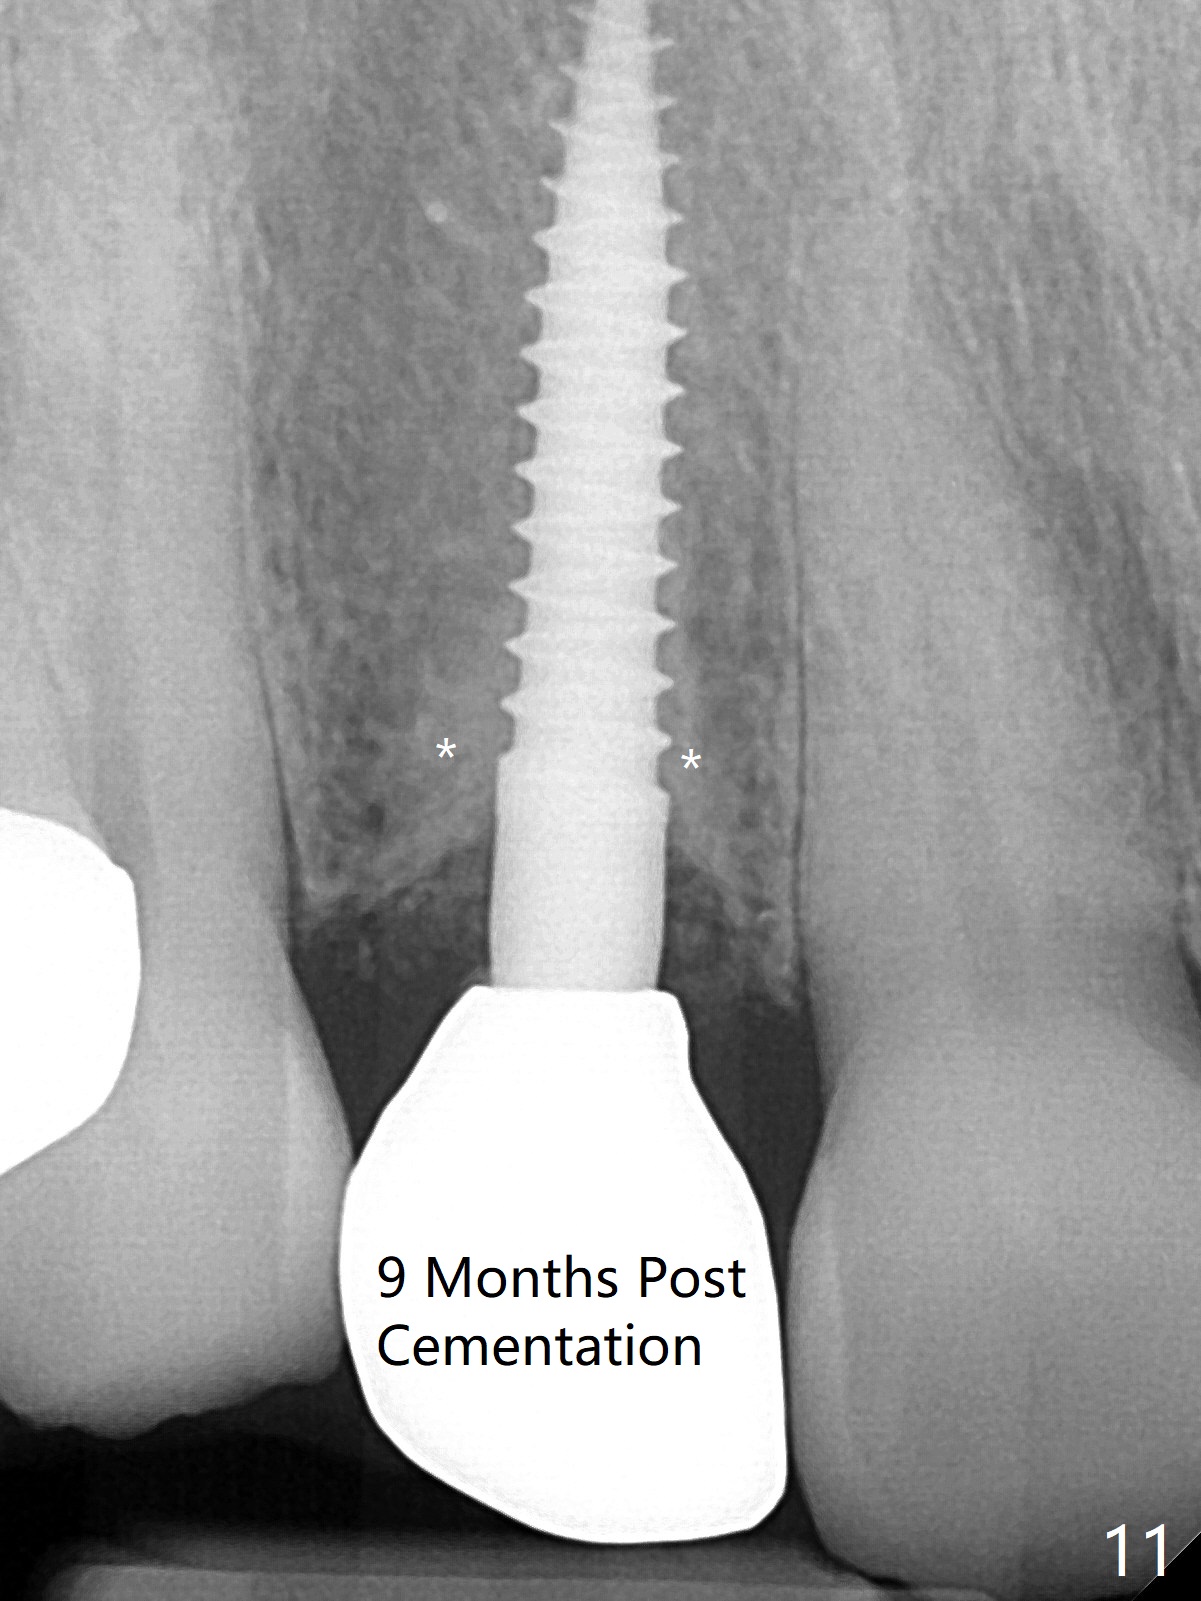

The rebonded crown at #7 debonds in a few days. There is deep anterior overbite and buccal concavity (Fig.1 *). The equigingival fracture (Fig.1,2) seems difficult to restore considering lack of posterior support (lower RPD in Fig.1). Buccal shield is tried in spite of the long root. It is not easy to tell whether the infected apex is removed due to the deep socket. In fact the apical buccal plate perforates because of use of surgical handpiece. Finally the buccal shied is removed. PA confirms the retained apex (Fig.3 *). The initial osteotomy with 1.5 mm drill in place is off trajectory (Fig.4). After adjustment of the trajectory of osteotomy (Fig.5), a 3x16(2) mm 1-piece implant is placed within normal limit (10-15 Ncm, Fig.6)). In fact bone graft is placed before (Fig.6,7 arrowhead; to repair apical buccal plate perforation) and after (Fig.6 *) implantation. The gingiva (including papillae) remains normal around the provisional 3 months postop (Fig.8). The bone graft becomes more organized 3 months postop (Fig.9), continues to do so 4.5 months postop (Fig.10) and becomes dense coronally 9 months post cementation (Fig.11: *).